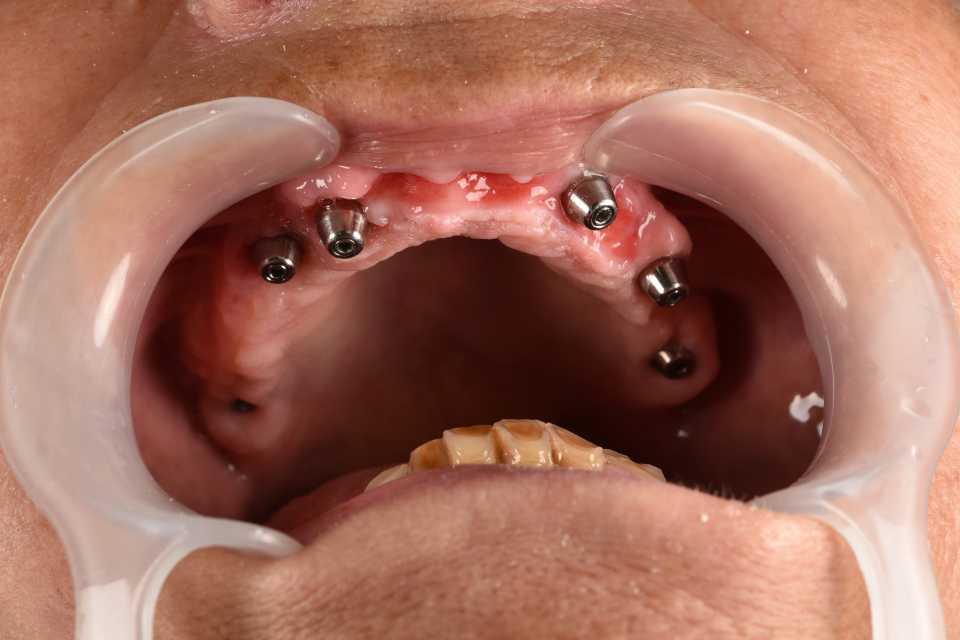

All on 6 cu implanturi orale speciale pterigoide, lucrare protezată din zirconiu pe suport de titan înșurubabilă

All on 6 cu implanturi orale speciale pterigoide, lucrare protezată din zirconiu pe suport de titan înșurubabilă.

Imaginile sunt prezentate în ordinea evoluției tratamentului, de la situația inițială la rezultatul final.